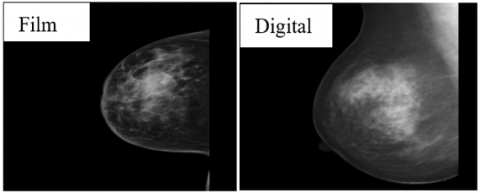

3. Dataset

Figure 1. Digital mammography with screen-film mammography